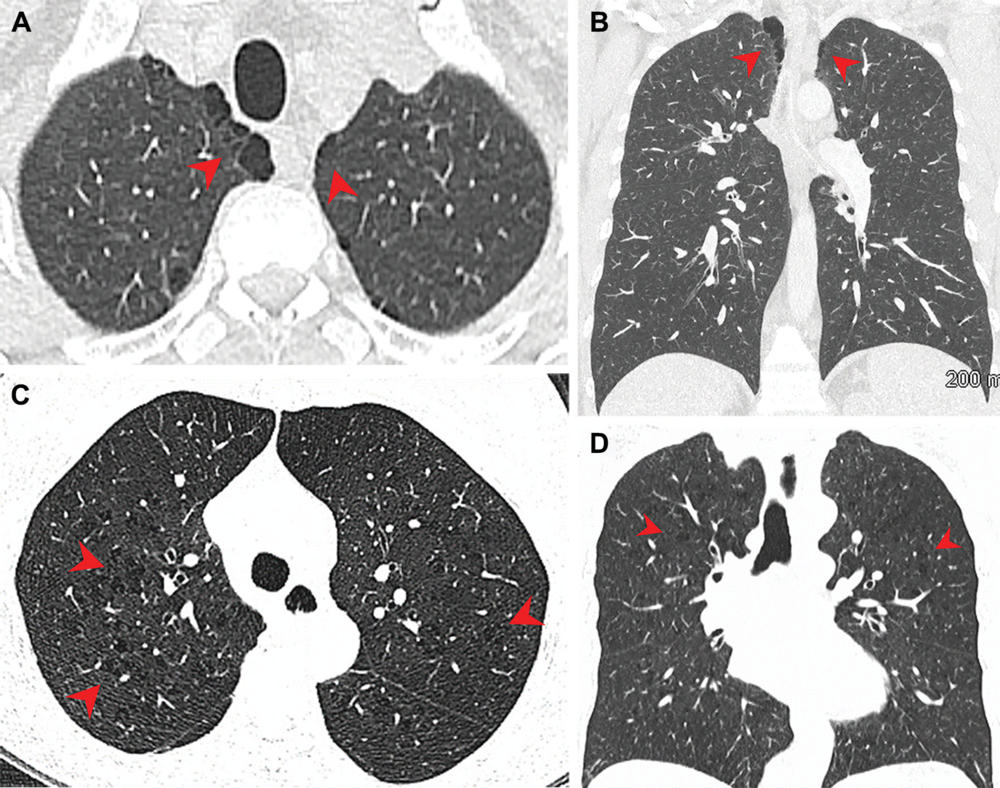

Figure 3. Pulmonary emphysema in (A, B) marijuana and (C, D) tobacco smokers. (A) Axial and (B) coronal CT images in a 44-year-old male marijuana smoker show paraseptal emphysema (arrowheads) in bilateral upper lobes. (C) Axial and (D) coronal CT images in a 66-year-old female tobacco smoker with centrilobular emphysema represented by areas of centrilobular lucency (arrowheads). (Murtha, et al.)